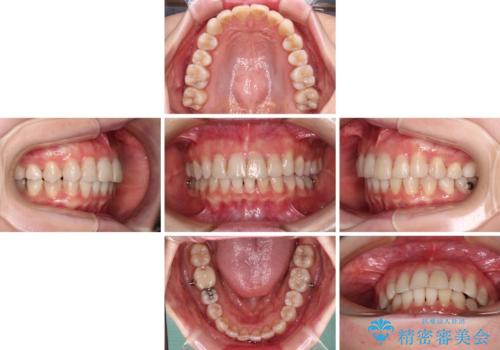

前歯の突出感とデコボコをインビザライン矯正で改善

- 上下前歯の突出感とデコボコを気にして来院された患者様です。

インビザラインによる上下歯列の側方拡大と後方移動、IPR(歯と歯の間を削る)にるスペースの獲得により歯列を整えることとしました。

骨格的な左右差があったため、上下の正中を合わせることができませんでした。

骨格の差は改善できないため、奥歯の咬み合わせに物足りなさを感じましたが、奥歯の咬み合わせによる不自由はなく、口元の突出感も改善することができました。